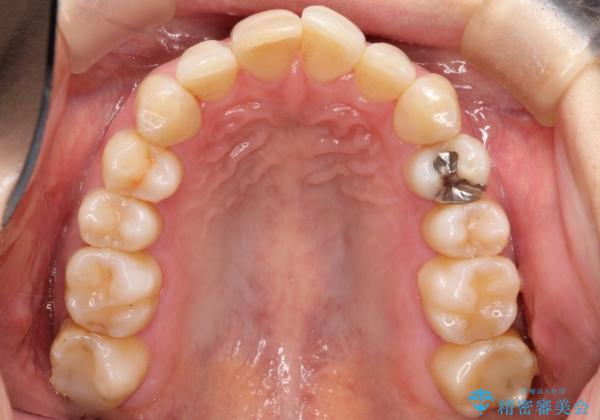

- 以前矯正をしていたが、わずかに後戻りをしてしまったのを主訴に来院されました。

装置はなるべくつけたくないとのことで、インビザラインにて治療することとなりました。

以前ワイヤー矯正をされていた方は、装置をつけての再矯正を希望されない方もいます。

その場合にインビザラインをお勧めさせていただいております。

後戻りがわずかな場合は、期間も短くて済む場合があります。